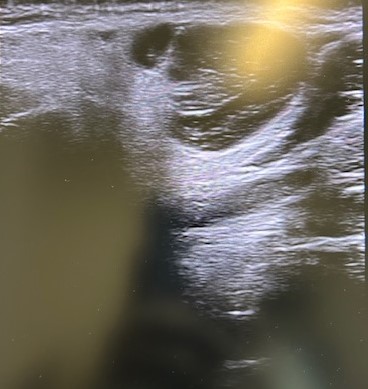

Ecografía POCUS: imagen heterogénea 1,9 x 1,7 asimétrica, con tabique en su interior, y captación de color (en modo C o con Doppler). Ante datos de mal de pronóstico solicitamos PAAF, analítica y ecografía reglada preferente.

Eco-PAAF: lesión sólida de morfología nodular posterior al ángulo mandibular derecho, con medidas aproximadas de 15 x 21 mm. Presenta ecoestructura heterogénea con áreas quísticas en su interior y con vascularización en el estudio Doppler.